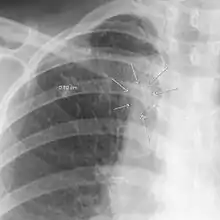

The arrows denote an ill-defined nodular opacity in medial aspect of right upper lobe with ill-defined rim of lucency surrounding it | |

Differential diagnosis | Aspergilloma |

In radiology, the air crescent sign is a finding on chest radiograph and computed tomography that is crescenteric and radiolucent, due to a lung cavity that is filled with air and has a round radiopaque mass.[1] Classically, it is due to an aspergilloma, a form of aspergillosis, that occurs when the fungus Aspergillus grows in a cavity in the lung.[2] It is also referred as Monad sign.[3]